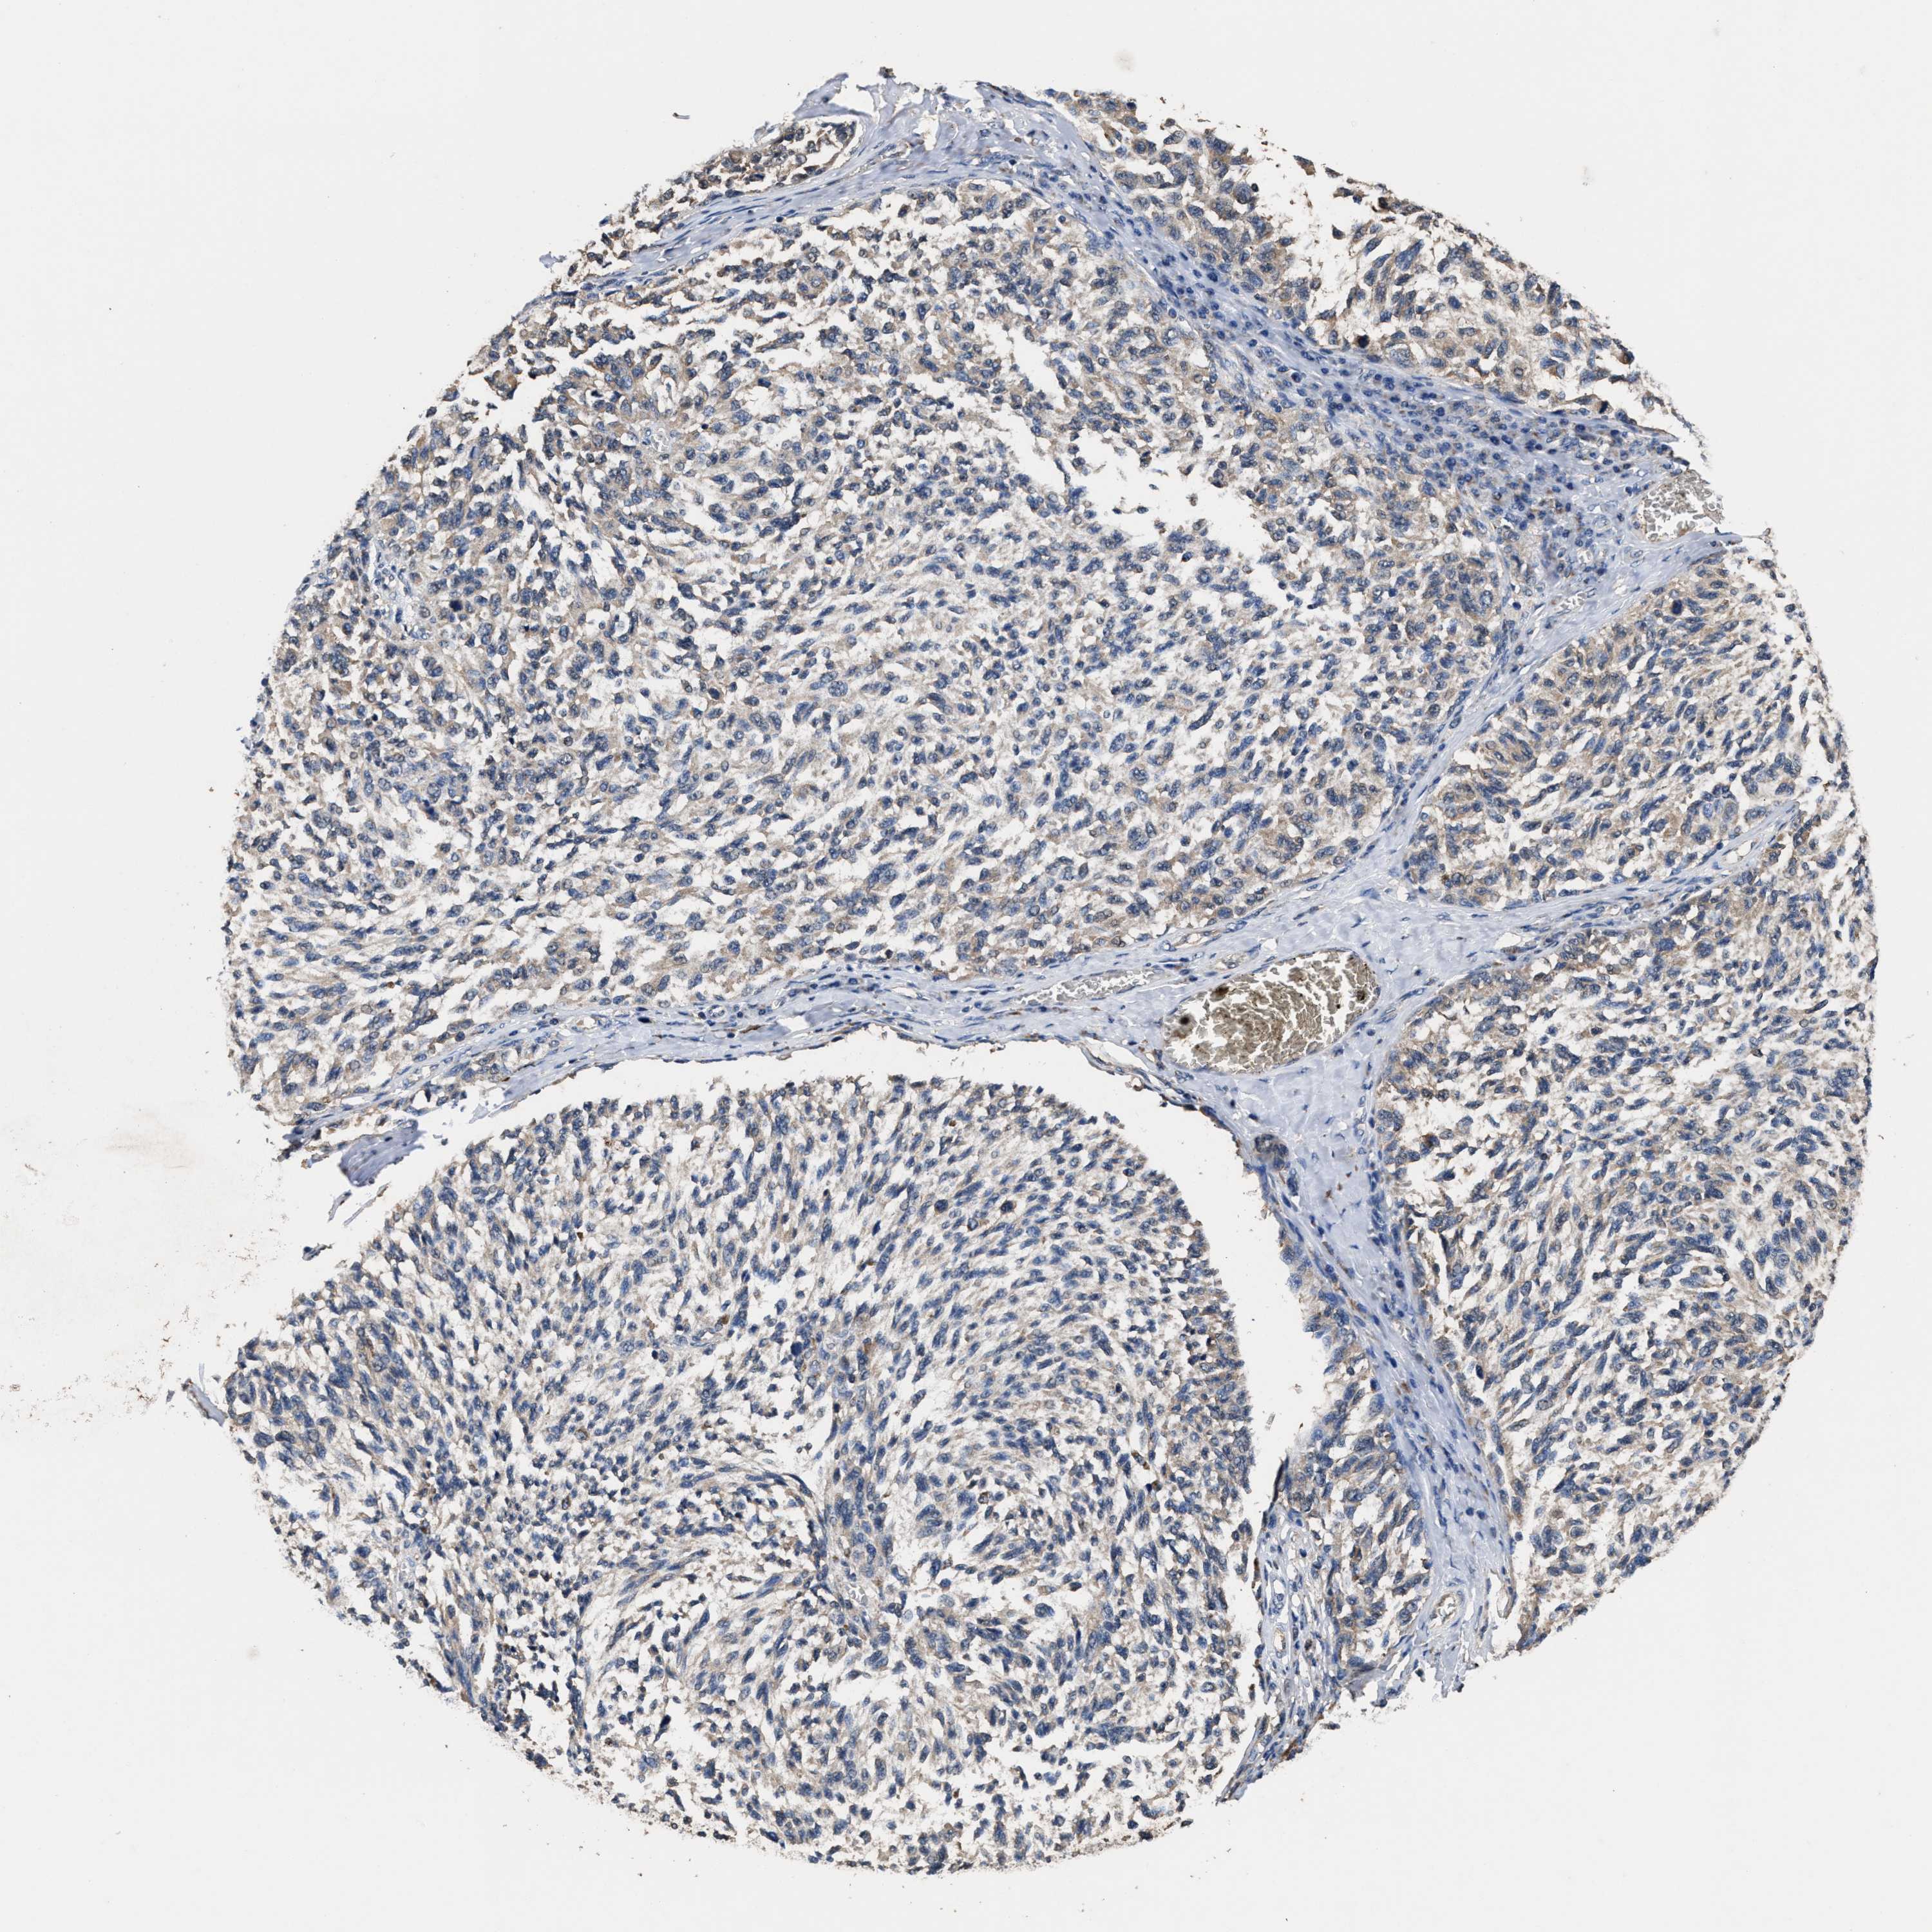

MELANOMA - Protein expressioni

A mouse-over function shows sample information and annotation data. Click on an image to view it in a full screen mode. Samples can be filtered based on level of antibody staining by selecting one or several of the following categories: high, medium, low and not detected. The assay and annotation is described here.

Note that samples used for immunohistochemistry by the Human Protein Atlas do not correspond to samples in the TCGA dataset.

Antibody stainingi

Antibody staining in the annotated cell types in the current human tissue is reported as not detected, low, medium, or high, based on conventional immunohistochemistry profiling in selected tissues. This score is based on the combination of the staining intensity and fraction of stained cells.

Each image is clickable and will lead to virtual microscopy that enables deeper exploration of all samples and also displays staining intensity scores, fraction scores and subcellular localization as well as patient and tissue information for each sample.

HPA022434

HPA022953

HPA022959

HPA028758

CAB007783

Staining

High

Medium

Low

Not detected

Intensity

Strong

Moderate

Weak

Negative

Quantity

>75%

75%-25%

<25%

None

Location

Nuclear

Cytoplasmic/membranous

Cytoplasmic/membranous,nuclear

Malignant melanoma, NOS

Malignant melanoma, Metastatic site